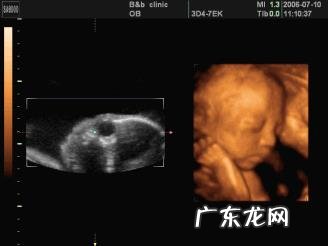

怀孕6个月,宝宝的四维拍照嘴巴和鼻子都好大,但是不代表宝宝生出来就很丑,因为四维照片并不代表宝宝的真实相貌 。

2.如果四维拍照时,胎儿在打哈欠,那么宝宝的嘴巴看起来就会很大 。

3.四维是动态的图像,就跟平时我们抓拍孩子的图片一样的 。

如果宝宝胎动比较厉害,那么抓拍的图像就会失真,宝宝看起来就会大鼻子大嘴巴,但是抓拍并不等于宝宝的真实相貌 。